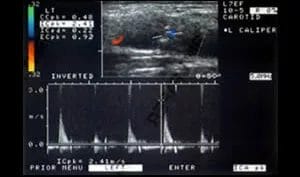

Internal Carotid Artery Stenosis

A patient presents with a known left hemisphere infarct, degree of internal carotid artery stenosis.

There is a critical stenosis of the left internal carotid artery (ICA) at its origin. Moderate irregularity and narrowing of the right ICA is noted at its origin. Carotid Doppler ultrasound quantifies the left ICA stenosis to be greater than 70% and the spectral waveform pattern suggests string flow or a near occlusion. The right ICA stenosis was measured at between 50-59%.